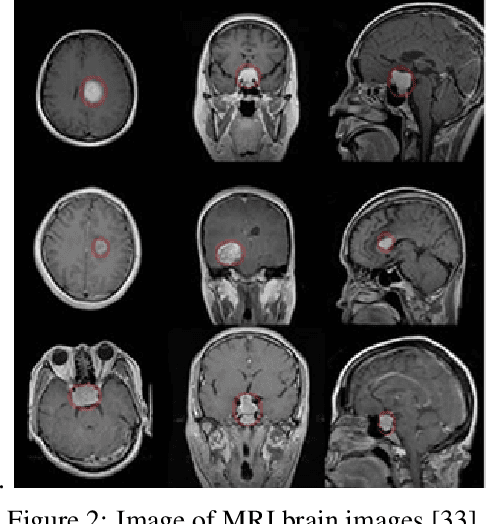

Abstract:The field of medical imaging is an essential aspect of the medical sciences, involving various forms of radiation to capture images of the internal tissues and organs of the body. These images provide vital information for clinical diagnosis, and in this chapter, we will explore the use of X-ray, MRI, and nuclear imaging in detecting severe illnesses. However, manual evaluation and storage of these images can be a challenging and time-consuming process. To address this issue, artificial intelligence (AI)-based techniques, particularly deep learning (DL), have become increasingly popular for systematic feature extraction and classification from imaging modalities, thereby aiding doctors in making rapid and accurate diagnoses. In this review study, we will focus on how AI-based approaches, particularly the use of Convolutional Neural Networks (CNN), can assist in disease detection through medical imaging technology. CNN is a commonly used approach for image analysis due to its ability to extract features from raw input images, and as such, will be the primary area of discussion in this study. Therefore, we have considered CNN as our discussion area in this study to diagnose ailments using medical imaging technology.

Abstract:The development of medical science greatly depends on the increased utilization of machine learning algorithms. By incorporating machine learning, the medical imaging field can significantly improve in terms of the speed and accuracy of the diagnostic process. Computed tomography (CT), magnetic resonance imaging (MRI), X-ray imaging, ultrasound imaging, and positron emission tomography (PET) are the most commonly used types of imaging data in the diagnosis process, and machine learning can aid in detecting diseases at an early stage. However, training machine learning models with limited annotated medical image data poses a challenge. The majority of medical image datasets have limited data, which can impede the pattern-learning process of machine-learning algorithms. Additionally, the lack of labeled data is another critical issue for machine learning. In this context, active learning techniques can be employed to address the challenge of limited annotated medical image data. Active learning involves iteratively selecting the most informative samples from a large pool of unlabeled data for annotation by experts. By actively selecting the most relevant and informative samples, active learning reduces the reliance on large amounts of labeled data and maximizes the model's learning capacity with minimal human labeling effort. By incorporating active learning into the training process, medical imaging machine learning models can make more efficient use of the available labeled data, improving their accuracy and performance. This approach allows medical professionals to focus their efforts on annotating the most critical cases, while the machine learning model actively learns from these annotated samples to improve its diagnostic capabilities.